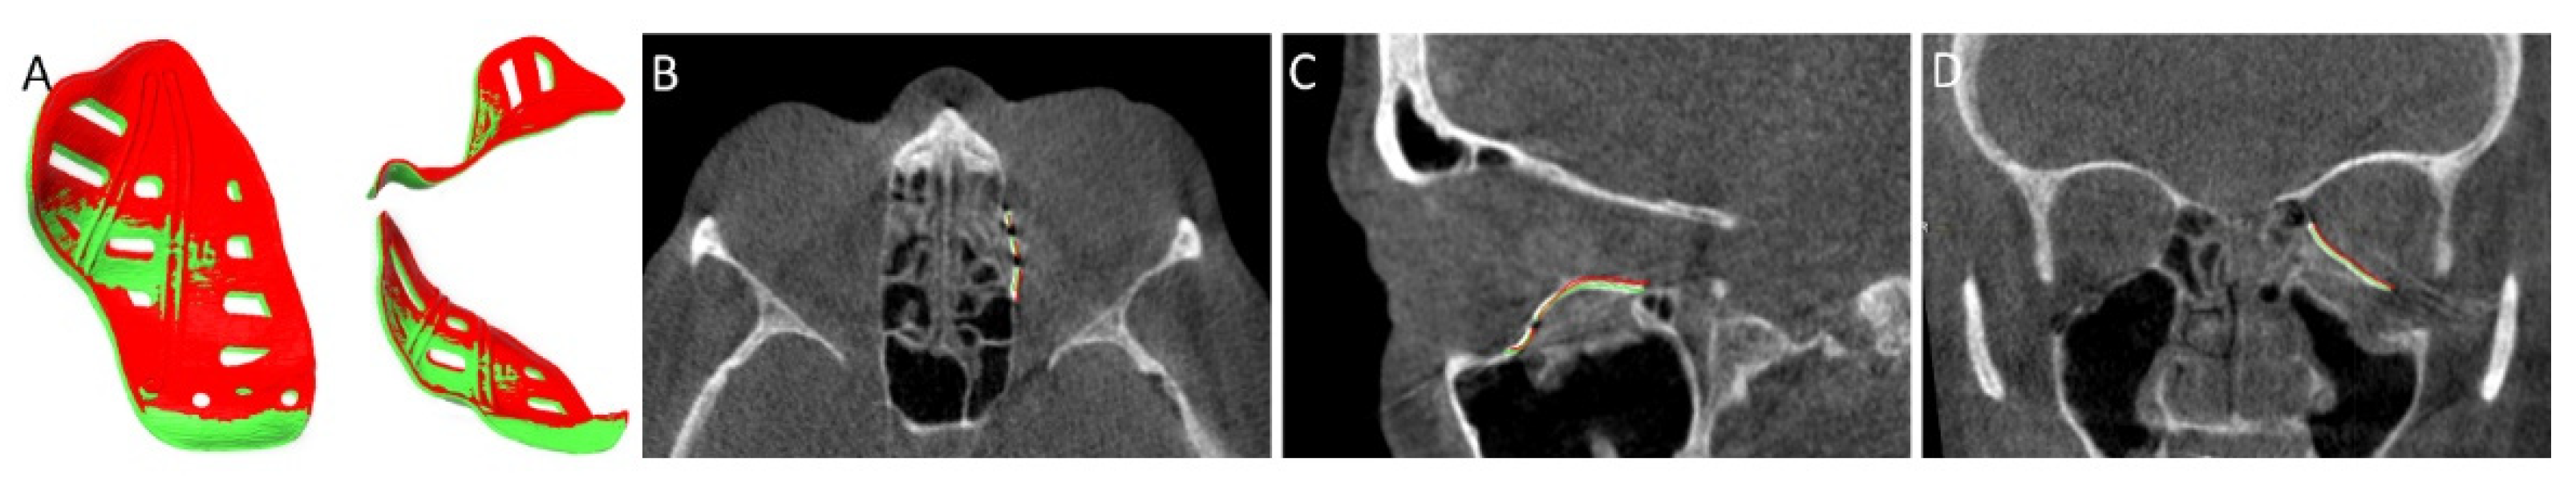

2.6. Evaluation